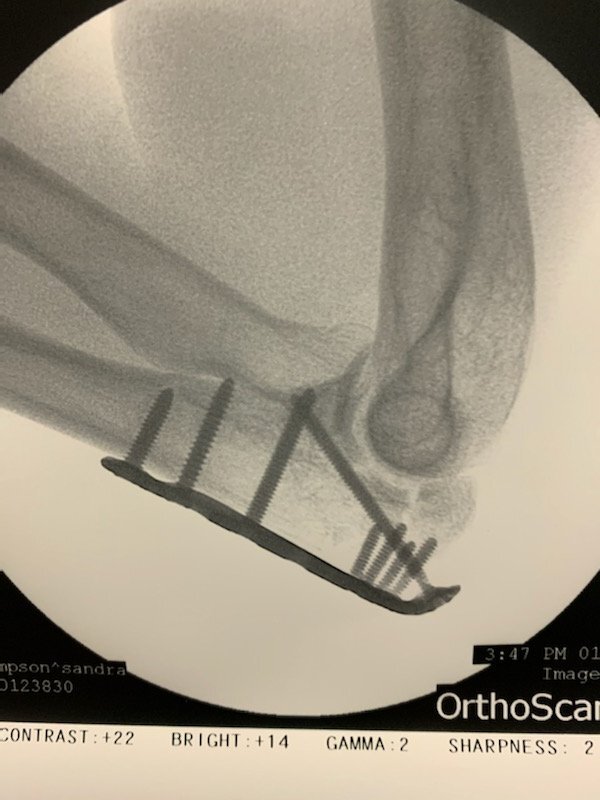

My elbow surgery was this past Monday afternoon and it went very smoothly. Well, all except for the cost of my insurance co-pay. :eek::scream: It was very helpful and reassuring to know both my orthopedic surgeon and my anesthesiologist both of whom I have ridden bicycles with in the past and continue to be friends with to this day. One cannot say that of the physicians in this country very often.

I've included a couple of post-op photos for your "viewing pleasure". ;):joy::joy: I'm quite sure my elbow is now stronger than it was before the operation.:rolleyes: My follow up appointment with my ortho doc is Friday afternoon so I'll know more about my recovery timeline after that. I'm hoping to get going on PT as soon as possible for both my elbow mobility and issues related to the pelvic bone fracture. We have motorcycle rides and trips planned! :grinning::cool:

IMG_7332.jpeg

IMG_7331.jpeg

IMG_7334.jpeg

omg. Just seen the X-ray pics. Hope you heal up quickly :heart: